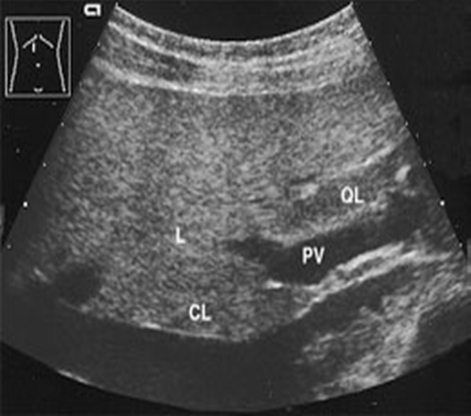

Ligamentum Venosum Falciform Ligament Ultrasound. The ligamentum venosum lies within a fissure on the inferior surface of the liver between the caudate lobe posteriorly and the left lobe anteriorly. Ali bajwa discusses the incidence of ligamentum teres tears and complete rupture, how does damage to the ligament happen? Xi whipple falciform ligament harvesting is shown. By dr tahir a siddiqui ( consultant sonologist ) gujranwala. Usually, it is attached to the left branch of the portal vein within the porta hepatis. Overview of ligaments coronary ligament triangular ligaments falciform ligament ligamentum teres hepatis ligamentum venosum hepatogastric and hepatoduodenal ligaments ligament of treitz gastrosplenic (gastrolienal) ligament gastrocolic ligament splenocolic ligament clinical. In utero, the ductus venosum was responsible for shunting blood from the left portal vein to the left hepatic. It is situated in an anteroposterior plane but lies obliquely so that one surface faces. The camera port (originally in port #2) was moved to port #4 for better. Falciform) and a remnant of the ventral mesentery of the fetus. The ligamentum venosum is the fibrous remnant of the ductus venosus of the fetal circulation. The falciform ligament normally consists of two closely applied layers of peritoneum and attaches the liver to the anterior abdominal wall. Extends from the umbilicus to the diaphragm in a sgittal plane and contains the ligamentum teres. The falciform ligament is a broad and thin peritoneal ligament. It may be continuous with the round ligament of liver.

Ligamentum falciforme (hepatis), falciform ligament of liver, ligamentum falciforme hepatis, ligament falciforme du foie. Xi whipple falciform ligament harvesting is shown. A novel member of the perivascular epithelioid clear cell family of tumors with a predilection for children and young… Falciform ligament definition it refers to a band of tough fibrous tissues which attach part of the liver to the abdominal and diaphragm wall. Das ligamentum falciforme spannt sich in anteroposteriorer richtung aus. These ligaments aren't like ligaments in joints which connect bones to bones. Transverse limb = porta hepatis = ( portal vein, hapatic artery + lymphatic vessels+ hepatic nerve plexus+ hepatic ducts that supply + drain the liver enter and leave it. What is the most likely cause of pernicious anemia (a chronic. Falciform ligament the second largest hepatic ligament is the falciform ligament. Ali bajwa discusses the incidence of ligamentum teres tears and complete rupture, how does damage to the ligament happen? The base of the falciform ligament goes down to the backwards and downwards, while its apex directed backward and upward. In utero, the ductus venosum was responsible for shunting blood from the left portal vein to the left hepatic. The falciform ligament is a ligament that attaches the liver to the anterior (ventral) body wall. The falciform ligament is a broad and thin peritoneal ligament. Ligamentum venosum ligamentum venosum the ligamentum venosum courses along the inferior aspect the ductus venosus (red), which becomes the ligamentum venosum, connects the umbilical vein medial umbilical ligament (see also median umbilical ligament and lateral umbilical ligament). Es ist aber leicht seitlich geneigt, so dass eine fläche nach vorn zur bauchwand weist, und hinter dem rechten musculus rectus. What structure is the hyperechoic. (this multiple choice question has been scrambled). Hypertrophy of ligamentum flavum leads to paralysis & disability. 852 x 574 jpeg 75 кб. Clear cell myomelanocytic tumor of the falciform ligament/ligamentum teres: It sits just underneath the diaphragm like this. The ligamentum venosum lies within a fissure on the inferior surface of the liver between the caudate lobe posteriorly and the left lobe anteriorly. It is a fold of the peritoneum (internal lining of abdominal. (this multiple choice question has been scrambled). If the ultrasound beam passes through a fatty tumor within the liver, and we know that the speed of sound in fat is lower than in soft tissue, where will this fatty tumor be placed? The falciform ligament divides the right and left lobes on the ____ surface. Its purpose is to help hold the liver in place inside the body. 2.1 views of the liver anterior, posterior, inferior. By dr tahir a siddiqui ( consultant sonologist ) gujranwala. The falciform ligament provides an attachment to the liver with the anterior abdominal wall.